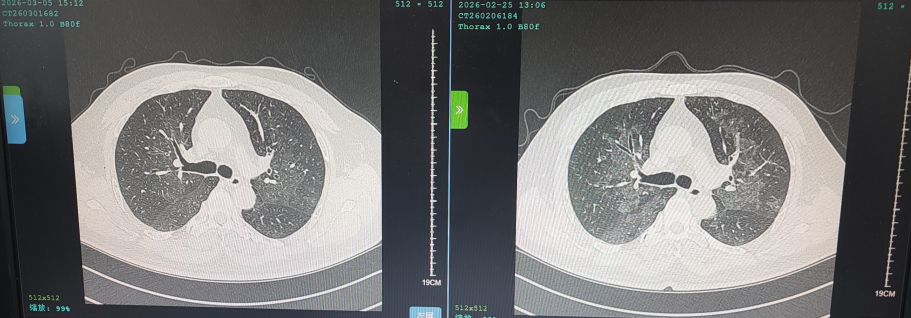

花鸟相伴本是生活雅趣,但鸟类羽毛碎屑、排泄物及粉尘中潜藏的有害物质,却可能悄然成为肺部健康的“隐形杀手”。这类疾病起病隐匿、症状不典型,极易被误诊或漏诊,严重时甚至可迅速进展为重症肺炎、呼吸衰竭,危及生命。近日,葫芦岛市第二人民医院呼吸与危重症医学科连续收治多例与接触鸟类密切相关的肺部疾病患者,为广大“养鸟一族”敲响警钟。 病例一:久咳不愈竟致呼吸衰竭 真凶竟是“养鸟过敏” 50岁的刘先生咳嗽、咳痰、气短两个月,严重时彻夜难眠,辗转求医无果,入院时已确诊I型呼吸衰竭。肺部影像学检查显示,双肺广泛存在磨玻璃影,局部已呈现“白肺”表现。此时,鉴别是感染性还是非感染性因素,成为诊断的关键。 ↑氧分压<60mmHg、二氧化碳氧分压正常、呼吸频率异常,呼吸衰竭 ↑相关检验项目正常,排除感染性因素 宋刚主任细致追问病史,发现其长期接触鸟类,结合支气管镜检查排除常见感染,最终明确诊断为外源性过敏性肺泡炎(过敏性肺炎),合并急性喘息性支气管炎。病因正是吸入鸟类羽毛及排泄物中的特异性蛋白过敏原,导致肺部过敏性炎症损伤。在脱离过敏原、接受经鼻高流量等规范治疗后,刘先生症状迅速缓解,顺利康复出院。 ↑左侧为治疗后肺部影像,右侧为治疗前肺部影像,肺炎明显减轻 病例二:高龄重症合并多重基础病 幕后黑手竟是鹦鹉热衣原体 86岁的杨大爷持续高热3天,体温达39℃,入院时已出现严重呼吸衰竭。更棘手的是,患者有20年再生障碍性贫血病史,白细胞、血小板极低,属典型免疫抑制,极易感染罕见病原菌。因血小板过低,行支气管镜检查出血风险极高。科室另辟蹊径,采用痰液NGS检测,精准锁定了致病元凶——鹦鹉热衣原体,这是一种经鸟类传播的非典型病原菌。 ↑鹦鹉热衣原体检测结果 ↑患者再生障碍性贫血,白细胞、血小板极低 诊断明确,治疗却面临两难:患者合并下肢静脉血栓,本应进行抗凝治疗,却因血小板严重低下受限。医疗团队综合研判、分层施策,严密监测血氧及肺栓塞风险,同步控制感染,并多次输注血小板、白蛋白及免疫球蛋白加强支持治疗。经综合救治,杨大爷病情好转,顺利出院。 ↑左侧为治疗前影像,右侧为治疗后影像,感染明显好转 病例三:体检发现肺部团块影 不是肺癌是真菌 患者养鸟多年,体检时发现右下肺团块状阴影,家属一度担心是肿瘤。但宋刚主任对比前年肺部影像,凭借丰富经验判断:恶性肿瘤在一年内长成如此大的团块相对少见,且病灶周围有典型晕征,高度怀疑是隐球菌肺炎——这是一种真菌性感染病,致病菌常寄生于鸟类粪便中。随后通过隐球菌荚膜多糖抗原检测,快速明确隐球菌肺炎诊断,规范抗真菌治疗后,病灶逐步缩小,病情控制稳定。 ↑隐球菌肺炎疗程较长,左侧为治疗后1个月的肺部影像,右侧为治疗前肺部影像,可见左侧晕征较右侧减轻 专家提醒:养鸟有风险 呼吸不适须警惕 宋刚主任表示,日常养鸟需做好防护: ☑ 注意环境卫生,保持通风干燥,控制粉尘; ☑ 定期清洁鸟笼与排泄物,清理时佩戴口罩、手套,避免直接接触; ☑ 老人、免疫低下、基础病较多者更需格外警惕。若出现长期咳嗽、气短、发热等症状,且有鸟类接触史,务必及时到专业呼吸科就诊,避免误诊漏诊。 我院呼吸与危重症医学科作为市级重点专科,致力于各类重症肺炎、呼吸衰竭、慢性气道疾病、哮喘等疾病的鉴别及规范化治疗,复杂疑难重症诊疗能力突出。同时携手中国医科大学附属第一医院,顶尖呼吸科专家每月定期来院出诊,让滨城百姓在家门口就能享受到省级优质医疗服务,为群众呼吸健康筑牢坚实屏障。 人民医院 人民名医 宋刚 主任医师 ·葫芦岛市第二人民医院呼吸与危重症医学科主任 ·辽宁省生命科学学会东北呼吸与危重症医学(PCCM)分会辽宁省基层委员会副主任委员 ·辽宁省细胞生物学学会放射粒子治疗专业委员会理事 ·辽宁省抗击新冠肺炎疫情先进个人 ·辽宁省预防医学会第一届吸烟相关疾病防治专业委员会委员 ·葫芦岛市劳动鉴定委员会专家库成员 ·葫芦岛市医学会呼吸内科学分会第三届委员会副主任委员 专业特色:擅长呼吸系统疑难及急危重患者的救治,如急慢性支气管炎、支气管哮喘、慢性阻塞性肺疾病、肺炎、肺栓塞、肺癌、间质性肺疾病、睡眠呼吸暂停综合征等,尤其擅长有创无创机械通气、支气管镜下相关检查及治疗(TBNA、气道支架置入术、球囊扩张等)、全肺灌洗术等领先技术,发表国家级期刊多篇。 出诊时间:每周二、周四全天 出诊地点:门诊二楼东侧35诊室 咨询热线:0429-8010115